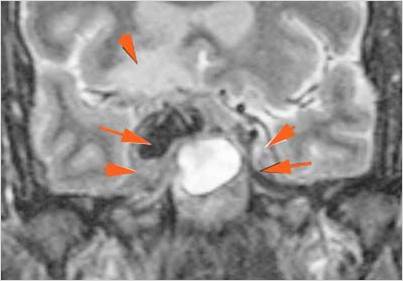

There is brain edema specifically involving the frontal and temporal lobes.

There is cerebritis specifically involving the frontal and temporal lobes.

There is brain abscess specifically involving the frontal and temporal lobes.